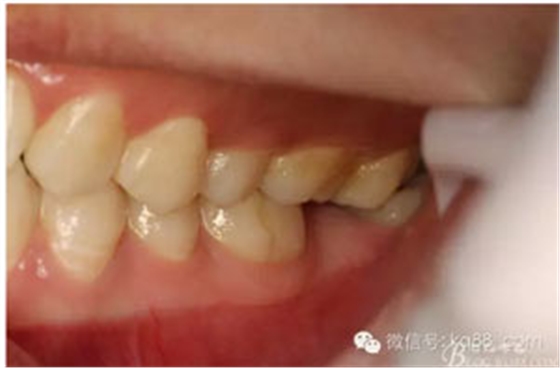

圖2.術(shù)前口內(nèi)照:37未萌出。38牙冠近中傾斜?;颊哒衬ど珴烧#瑹o瘺管、無滲出。

圖3。閉口位,27與38有咬合接觸。因此,保留38、拔除37.防止囊性變進(jìn)一步擴(kuò)大。